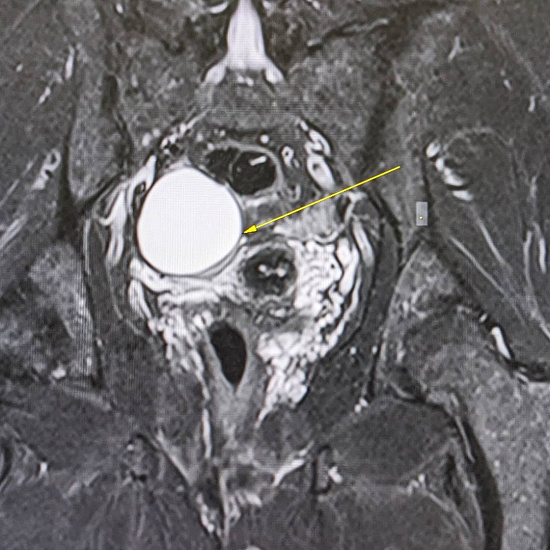

53-летняя пациентка обратилась к гинекологу в рамках программы check-up. При осмотре документации выяснилось, что на проведенных УЗИ-исследованиях от 2021 и 2023 года определяется образование правого яичника, требующее дифференциальной диагностики между эндометриоидной кистой и кистозно измененным яичником.

С целью оценки образования, уточнения его структуры и динамики роста пациентке было проведено МРТ органов малого таза.

При МРТ было выявлено жидкостное кистозное образование правого яичника без папиллярных разрастаний, гораздо больших размеров относительно первоначального УЗИ-исследования.

Учитывая анамнез пациентки, особенности структуры и размеры образования, была заподозрена цистаденома.

Пациентка направлена на повторную консультацию к гинекологу с последующим удалением данного образования, учитывая отрицательную динамику роста.